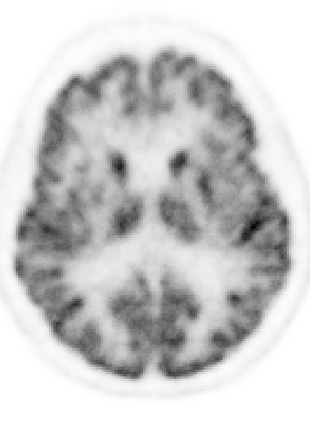

Due to various physical degradation factors and limited counts received, PET image quality needs further improvements. The denoising diffusion probabilistic models (DDPM) are distribution learning-based models, which try to transform a normal distribution into a specific data distribution based on iterative refinements. In this work, we proposed and evaluated different DDPM-based methods for PET image denoising. Under the DDPM framework, one way to perform PET image denoising is to provide the PET image and/or the prior image as the network input. Another way is to supply the prior image as the input with the PET image included in the refinement steps, which can fit for scenarios of different noise levels. 120 18F-FDG datasets and 140 18F-MK-6240 datasets were utilized to evaluate the proposed DDPM-based methods. Quantification show that the DDPM-based frameworks with PET information included can generate better results than the nonlocal mean and Unet-based denoising methods. Adding additional MR prior in the model can help achieve better performance and further reduce the uncertainty during image denoising. Solely relying on MR prior while ignoring the PET information can result in large bias. Regional and surface quantification shows that employing MR prior as the network input while embedding PET image as a data-consistency constraint during inference can achieve the best performance. In summary, DDPM-based PET image denoising is a flexible framework, which can efficiently utilize prior information and achieve better performance than the nonlocal mean and Unet-based denoising methods.